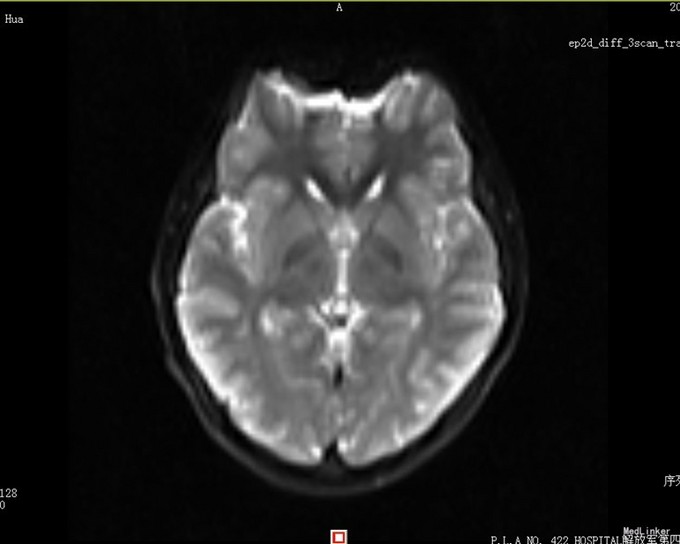

患者,男,14岁,患者自2周前不慎因外伤后出现头痛、头晕,为持续性钝痛,以后枕部为主,无发热畏寒,无视物模糊,无胸闷气短等不适,当时未引起足够重视,后患者感症状持续存在,遂告诉家人,家人送到我院门诊就诊,查头颅CT示:1、双侧大脑半卵圆中心区见多发斑片状低密度影,考虑血管间隙扩大可能,建议MRI复查;2、双侧额窦、筛窦炎。为进一步检查及治疗入院。患者目前精神欠佳,体力下降,食欲正常,睡眠正常,体重无明显变化,大便正常,排尿正常。既往体健。

患者目前诊断:1、脑外伤后综合征;2、半卵圆中心区血管间隙扩大;给予改善循环、营养神经等对症治疗,患者头痛、头晕症状明显好转。